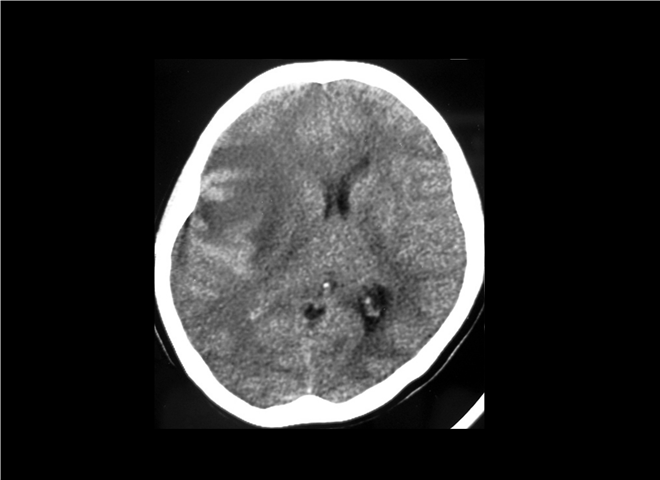

13_CT增强扫描